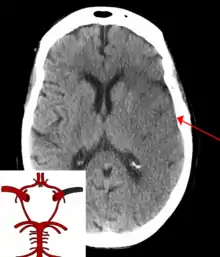

![]() | |

| CT scan of the brain showing a prior right-sided ischemic stroke from blockage of an artery. Changes on a CT may not be visible early on.[1] | |

The biggest risk factor for stroke is high blood pressure.[7] Other risk factors include high blood cholesterol, tobacco smoking, obesity, diabetes mellitus, a previous TIA, end-stage kidney disease, and atrial fibrillation.[2][7][8] Ischemic stroke is typically caused by blockage of a blood vessel, though there are also less common causes.[13][14][15] Hemorrhagic stroke is caused by either bleeding directly into the brain or into the space between the brain's membranes.[13][16] Bleeding may occur due to a ruptured brain aneurysm.[13] Diagnosis is typically based on a physical exam and supported by medical imaging such as a CT scan or MRI scan.[9] A CT scan can rule out bleeding, but may not necessarily rule out ischemia, which early on typically does not show up on a CT scan.[10] Other tests such as an electrocardiogram (ECG) and blood tests are done to determine risk factors and rule out other possible causes.[9] Low blood sugar may cause similar symptoms.[9]

Stroke is diagnosed through several techniques: a neurological examination (such as the NIHSS), CT scans (most often without contrast enhancements) or MRI scans, Doppler ultrasound, and arteriography. The diagnosis of stroke itself is clinical, with assistance from the imaging techniques. Imaging techniques also assist in determining the subtypes and cause of stroke. There is yet no commonly used blood test for the stroke diagnosis itself, though blood tests may be of help in finding out the likely cause of stroke.[68] In deceased people, an autopsy of stroke may help establishing the time between stroke onset and death.

Imaging

For diagnosing ischemic (blockage) stroke in the emergency setting:[69]

- CT scans (without contrast enhancements)

- sensitivity= 16% (less than 10% within first 3 hours of symptom onset)

- specificity= 96%

- MRI scan

- sensitivity= 83%

- specificity= 98%

For diagnosing hemorrhagic stroke in the emergency setting:

- sensitivity= 89%

- specificity= 100%

- sensitivity= 81%

For detecting chronic hemorrhages, an MRI scan is more sensitive.[70]

CT scans may not detect ischemic stroke, especially if it is small, of recent onset,[10] or in the brainstem or cerebellum areas (posterior circulation infarct). MRI is better at detecting a posterior circulation infarct with diffusion-weighted imaging.[71] A CT scan is used more to rule out certain stroke mimics and detect bleeding.[10] The presence of leptomeningeal collateral circulation in the brain is associated with better clinical outcomes after recanalization treatment.[72] Cerebrovascular reserve capacity is another factor that affects stroke outcome – it is the amount of increase in cerebral blood flow after a purposeful stimulation of blood flow by the physician, such as by giving inhaled carbon dioxide or intravenous acetazolamide. The increase in blood flow can be measured by PET scan or transcranial doppler sonography.[73] However, in people with obstruction of the internal carotid artery of one side, the presence of leptomeningeal collateral circulation is associated with reduced cerebral reserve capacity.[74]